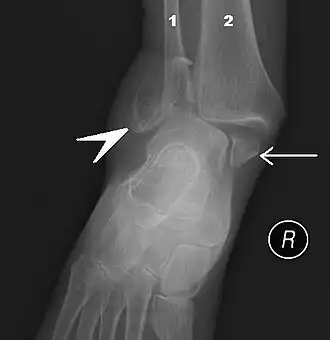

Röntgendiagnostiek is enkel geïndiceerd wanneer er sprake is van pijn in de malleoli of in de middenvoet en daarenboven een van volgende symptomen zich voordoet:

- Pijn bij palpatie van de distale 6 cm van de posterieure zijde van het scheenbeen of de knobbel van de binnenenkel;

- Pijn bij palpatie van de distale 6 cm van de posterieure zijde van het kuitbeen of het uiteinde van de buitenste enkelknobbel;

- Pijn bij palpatie van de basis van het voetwortelbeentje van de kleine teen;

- Pijn bij palpatie van het os naviculare.